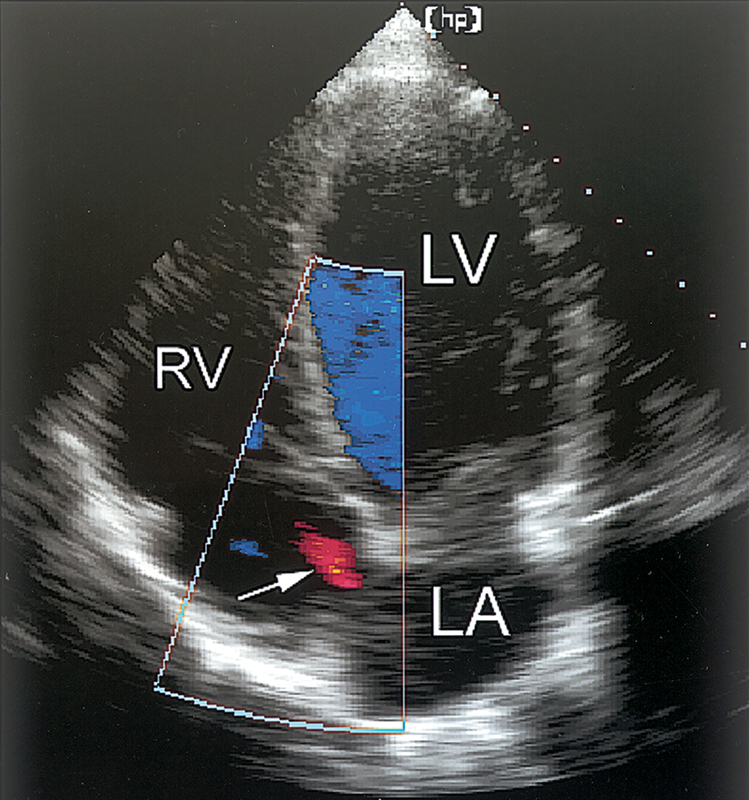

فحوصات تشخيصية لبعض امراض القلب والشرايين التاجية